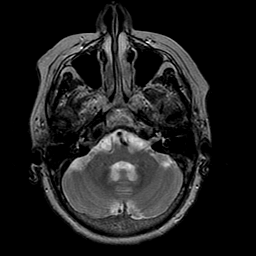

Stroke:T2-weighted MR #1 -- Slice #5

[Home][Help][Clinical] Slice 5